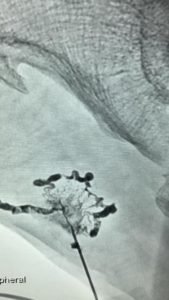

SCLEROTHERAPY

This is the mainstay of treatment of most CVMs, in which single or multiple sessions of injections of sclerosant solution (STS, bleomycin or alcohol) are given in the lesion under Doppler or fluoroscopy guidance.

Although initially patient can feel hardness or bruising at the injection site, this treatment can eventually help to reduce the size of the swelling.